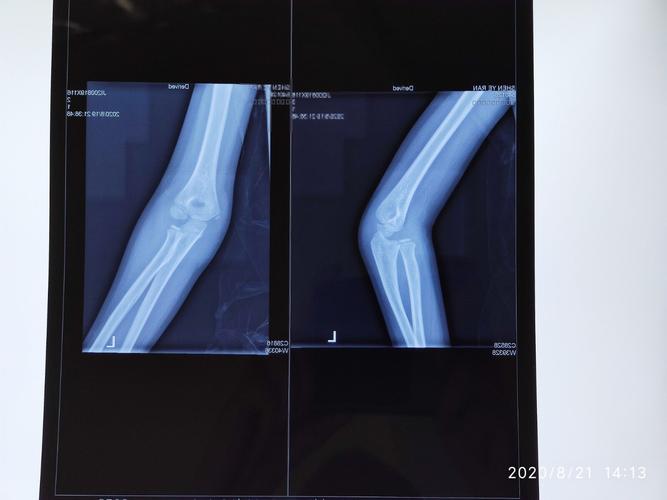

儿童孟氏骨折

儿童骨折的陷阱:儿童孟氏骨折脱位

小儿孟氏骨折图片